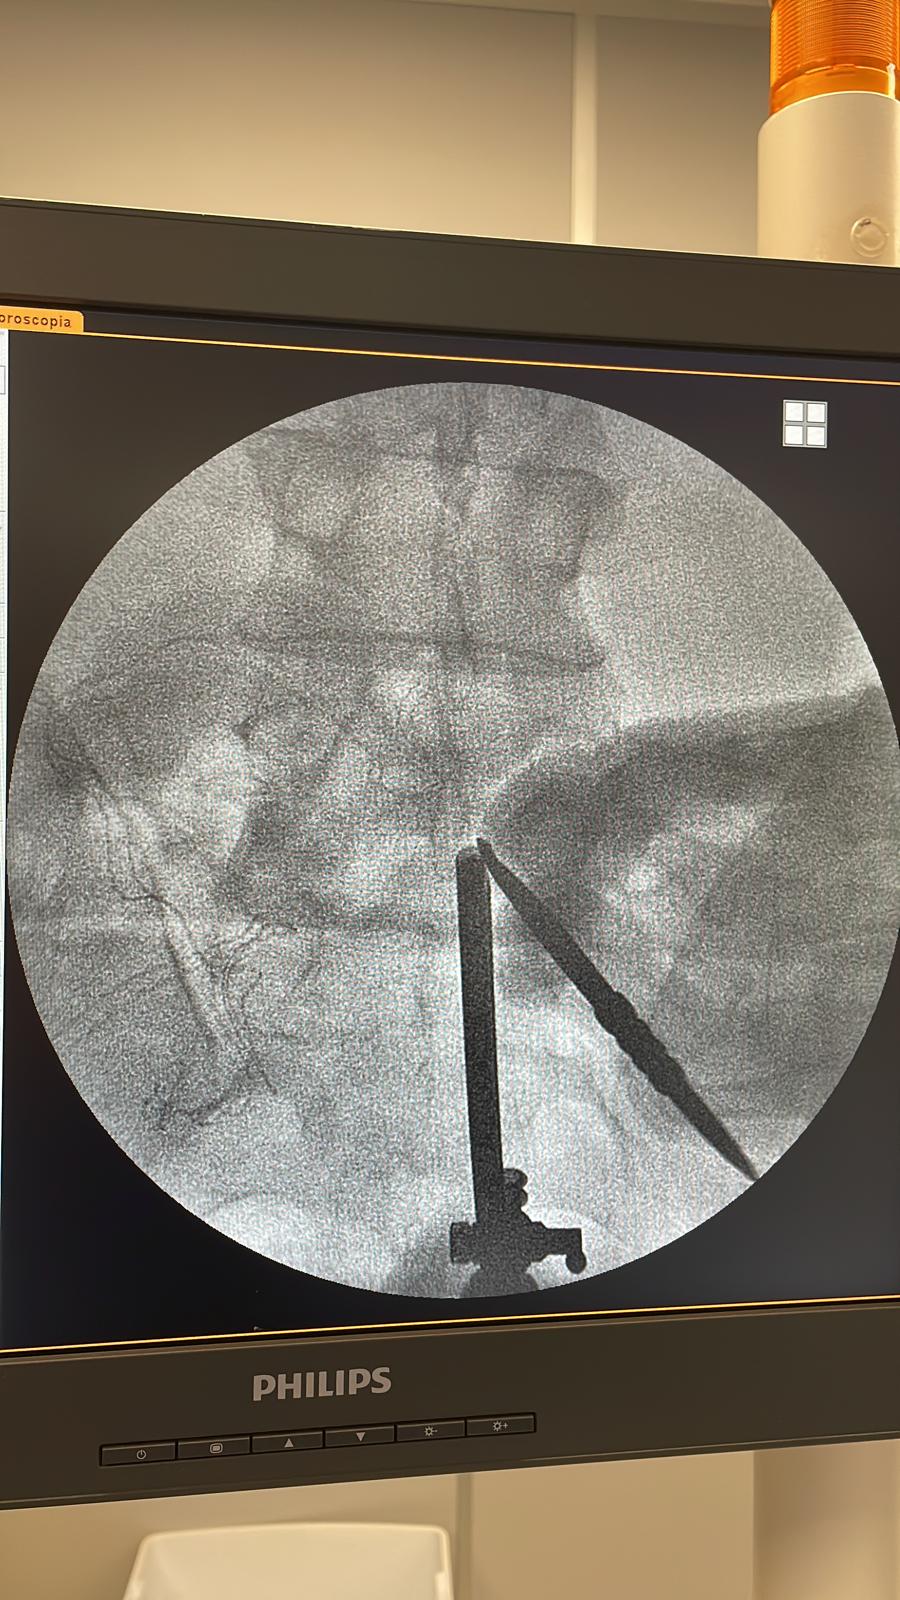

Se trata de una técnica mini-invasiva de cirugía de columna en la que el acceso es a través de una única incisión por la que se introduce el set de trabajo endoscopico que consta de cámara, luz, irrigación y cánula de trabajo.

Las patologías más frecuentes a tratar son: estenosis de canal, hernia de disco lumbar, estenosis del receso lateral, estenosis foraminal.

Se trata de una técnica mini-invasiva de cirugía de columna en la que el acceso es a través de una incisión de por la que se introduce la cámara con aporte de luz e irrigación y una segunda incisión para el portal de trabajo.

Las patologías más frecuentes a tratar son: estenosis de canal, hernia de disco lumbar, estenosis del receso lateral.

• Discectomía Endoscópica

En la discectomía endoscópica, se realiza una pequeña incisión por la que se introduce un endoscopio (un tubo delgado con una cámara y luz) para visualizar y remover el material del disco herniado. Este método permite al cirujano trabajar con precisión y minimizar el daño a los tejidos circundantes.